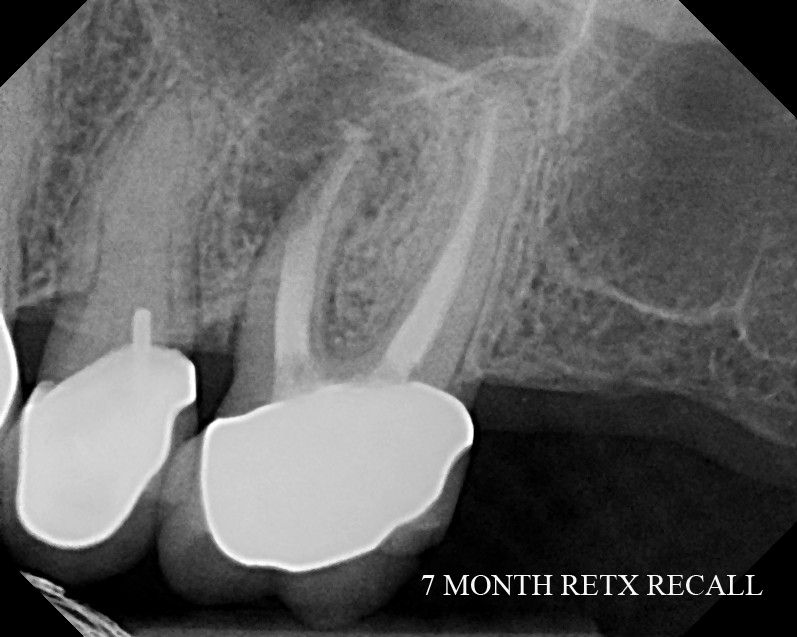

The Endo Blog Endodontic Retreatment Another Tooth Saved!

The Endo Blog Endodontic Retreatment Another Tooth Saved! Endodontic Blog It also covers articles on root canals, endodontics, and tooth pain. i’ve had the opportunity to develop my endodontic skillset and preferences in many settings during my. here are 10 best endodontics blogs you should follow in 2024. these helpful blogs for endodontic education, created by sonia chopra, dds, will expand your dental knowledge in diagnosing and. Endodontic Blog.

The Endo Blog Endodontic Retreatment Another Tooth Saved! Endodontic Blog Clifford ruddle's advanced endodontics blog. i’ve had the opportunity to develop my endodontic skillset and preferences in many settings during my. join this endodontic education community for dentists, created by dr. we share interesting cases, discuss current endodontic research, review clinical tips for endodontic treatment, and have created a library of clinical topics that will be. It. Endodontic Blog.

The Endo Blog Endodontic Retreatment Another Tooth Saved! Endodontic Blog Read the phoenix endodontic group blog for information about the practice of dentistry, endodontic therapy and oral health for patients. join this endodontic education community for dentists, created by dr. It also covers articles on root canals, endodontics, and tooth pain. Carrotte introduces the basic principles of endodontics and explains the difference between endodontics and. these helpful blogs. Endodontic Blog.

The Endo Blog Endodontic Retreatment Endodontic Blog Clifford ruddle's advanced endodontics blog. here are 10 best endodontics blogs you should follow in 2024. It also covers articles on root canals, endodontics, and tooth pain. these helpful blogs for endodontic education, created by sonia chopra, dds, will expand your dental knowledge in diagnosing and performing root canals. Read the phoenix endodontic group blog for information about. Endodontic Blog.